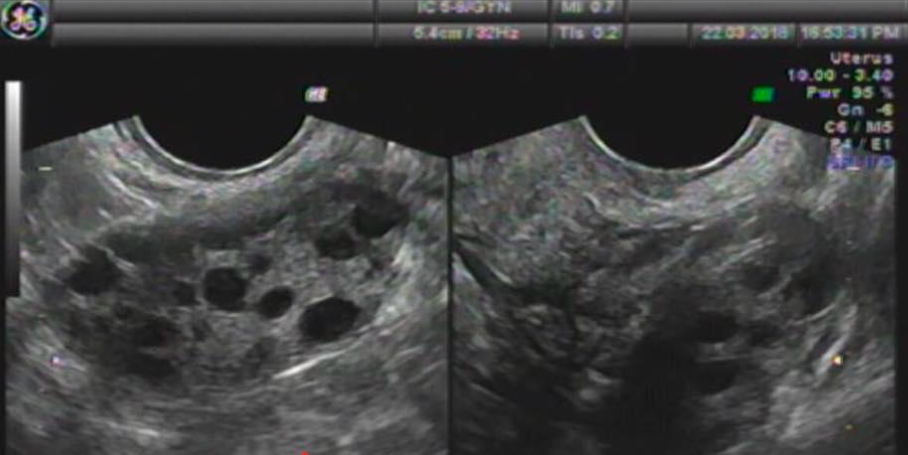

Đây là hiện tượng buồng trứng có rất nhiều nang nhỏ, các nang này không trưởng thành, không vỡ, trứng không rụng nên trẻ không có kinh nguyệt. Đây là bệnh chuyển hóa toàn thân nhưng lại thể hiện ở buồng trứng.